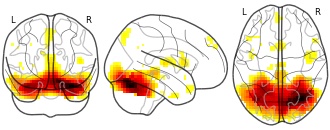

"description": "Abnormal gray matter in BPD. Brain regions with significant heterogeneity (i.e. between-study variance) in the comparison of patients with BPD and healthy controls. Results are thresholded at at p<.005 & k>20. Note: Results are based on meta-analysis of group comparisons. Note2: Results were updated (see Erratum for this publication)",